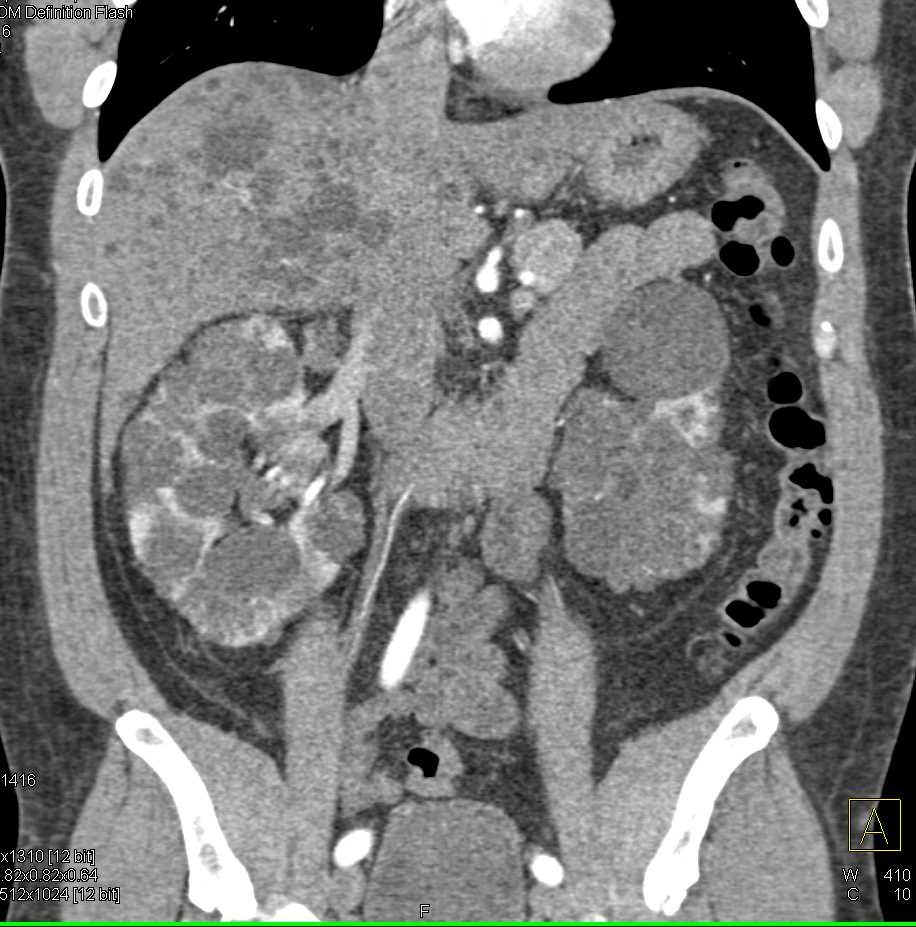

Incidental Fibromuscular Dysplasia (FMD) Right Renal Artery in Patient with Pelvic Hematoma